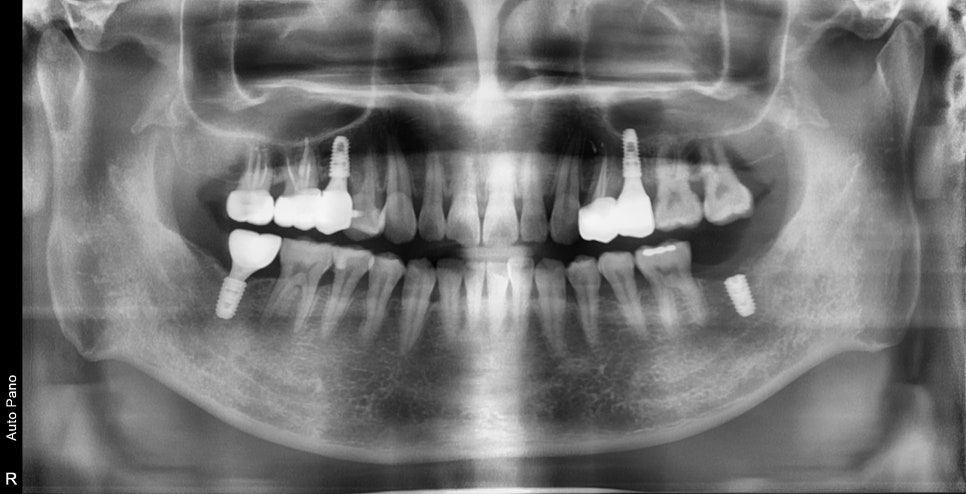

엑스레이, 구강 내 사진을 보게 되면 여러 종류의 치료가 필요한 부위들이 보입니다

충치로 인한 심미적인 부분, 치아 상실 부위, 대합 치아가 없다 보니 아래로 내려온 치아,

깊은 충치로 인한 신경치료가 필요한 치아까지

좌우 다수의 치아에서 치료가 필요했습니다.

일단 가장 오래 걸리는 임플란트 먼저 수술을 했습니다.

아쉽게도 한 부위는 발치한지 얼마 안 되었기 때문에

바로 수술이 불가능하였고 추후에 뼈가 회복되고 진행하기로 했습니다.

표시된 부분은 신경치료가 진행되었습니다.

충치가 깊은 치아도 있었고 대합 치아의 부재로 인한

치아가 너무 많이 내려가 있어 신경치료+보철치료를 하지 않으면

치아의 높이를 맞출 수가 없었습니다.